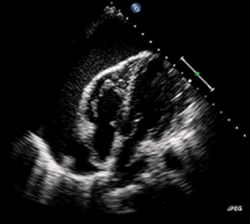

Echocardiogram (ultrasound): when pericardial effusion is suspected, echocardiography usually confirms the diagnosis and allows assessment of the size, location and signs of hemodynamic instability.[4] A transthoracic echocardiogram (TTE) is usually sufficient to evaluate pericardial effusion and it may also help distinguish pericardial effusion from pleural effusion and MI. Most pericardial effusions appear as an anechoic area (black or without an echo) between the visceral and the parietal membrane.[1] Complex or malignant effusions are more heterogeneous in appearance, meaning they may have variations in echo on ultrasound.[5] TTE can also differentiate pericardial effusion based on the size. Although it's difficult to define size classifications because they vary with institutions, most commonly they are as follows: small <10, moderate 10–20, large >20.[5] An echocardiogram is urgently needed for evaluation when there is concern for hemodynamic compromise, a rapidly developing effusion or history of recent cardiac surgery/procedures.[1]

A large anechoic (black) pericardial effusion as seen on ultrasound. Closed arrow: the heart, open arrow: the effusion -